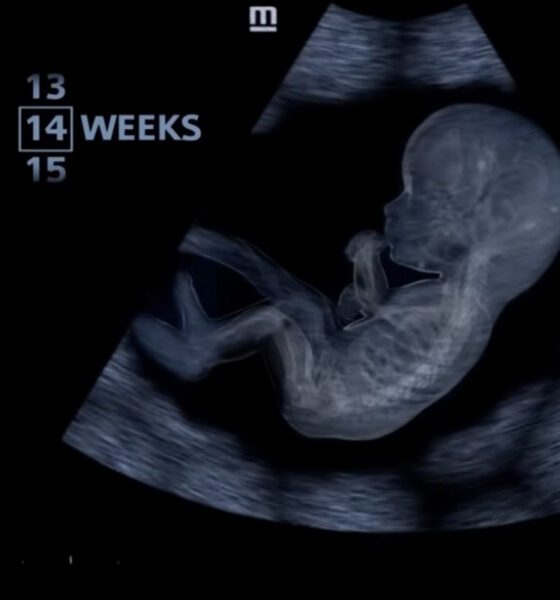

El video muestra las 14 semanas de gestación después de la fecundación. Aunque se trata de una etapa temprana del embarazo, los brazos y las piernas han comenzado a desarrollarse.

También revela que el sistema nervioso del bebé se está desarrollando rápidamente, formando nuevas conexiones entre el cerebro y el cuerpo. El corazón se fortalece cada vez más. Ahora late un poco más despacio que al principio del embarazo, a unas 150 pulsaciones por minuto.